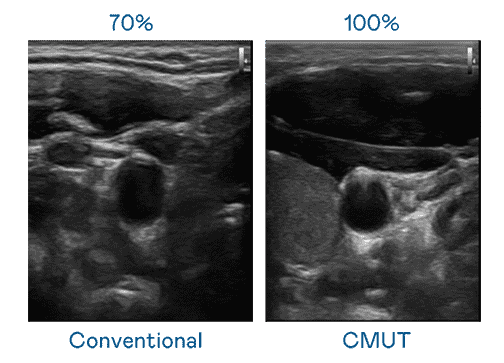

CMUT 技术是一种用电容式微机电元件来产生超音波讯号的技术。。。与传统 PZT 压电式技术相比,,,,CMUT 频宽增加 30%,,更宽频的超音波讯号让影像解析度大幅提升,,,,是实现高影像品质医疗超音波扫描、、、促进精准医疗发展的关键技术。。

大频宽带来超清晰影像

超音波影像的解析度高低,,,,首先取决于探头能发出的讯号频宽。。。。z6尊龙 CMUT 可提供高清晰的超音波讯号,,,,提供高频宽、、高灵敏度、、、影像纹理细节更高的超音波影像,,协助医护人员缩短影像判读时间及利用精准的医疗影像进行诊断。。。。